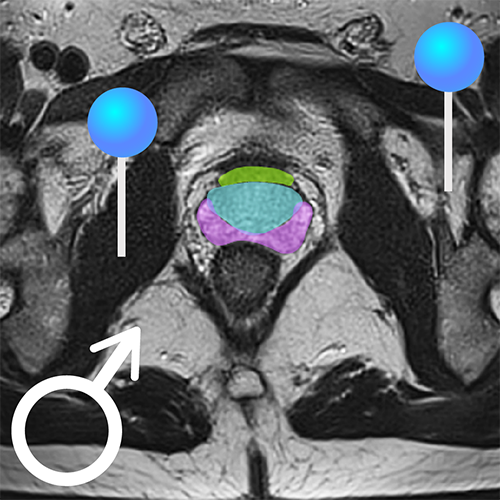

Анатомия малого таза: КТ-изображения для подробного изучения